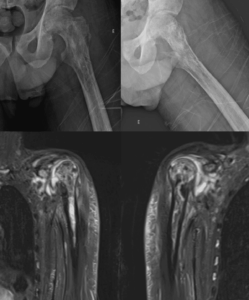

Paciente, 30 anos, sexo masculino, com diagnóstico prévio de anemia falciforme, buscou atendimento médico devido ao quadro de dor intensa e saída de secreção purulenta no quadril esquerdo, além de dor em ombros. Foi internado para investigação e tratamento. Dentre os exames realizados, temos os seguintes achados: